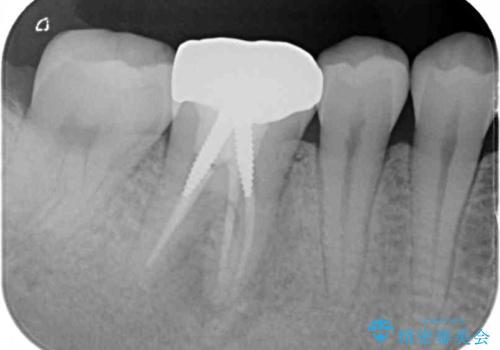

銀のクラウンが装着されていた歯は根管治療が必要であり、その奥の歯は大きな詰め物の隙間が虫歯になってしみていました。

根管治療などを行った後に、オールセラミッククラウンにて補綴することとしました。